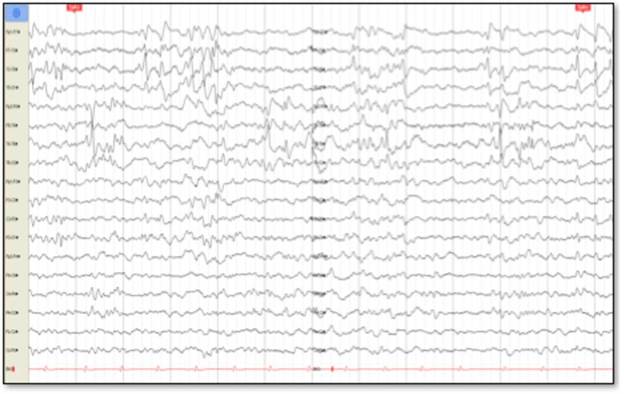

Cerebral nuclear magnetic resonance (NMR) showed generalized cortical atrophy and bilateral hippocampal atrophy (Figure 1), while electroencephalogram revealed independent bilateral temporal ictal activity, frequently associated with bradycardia and hypoxemia (Figure 2).

Except for the presence of burst suppression in barbiturate coma, EEG shows multi focal activity with greater involvement of the temporal and frontal lobes 4.